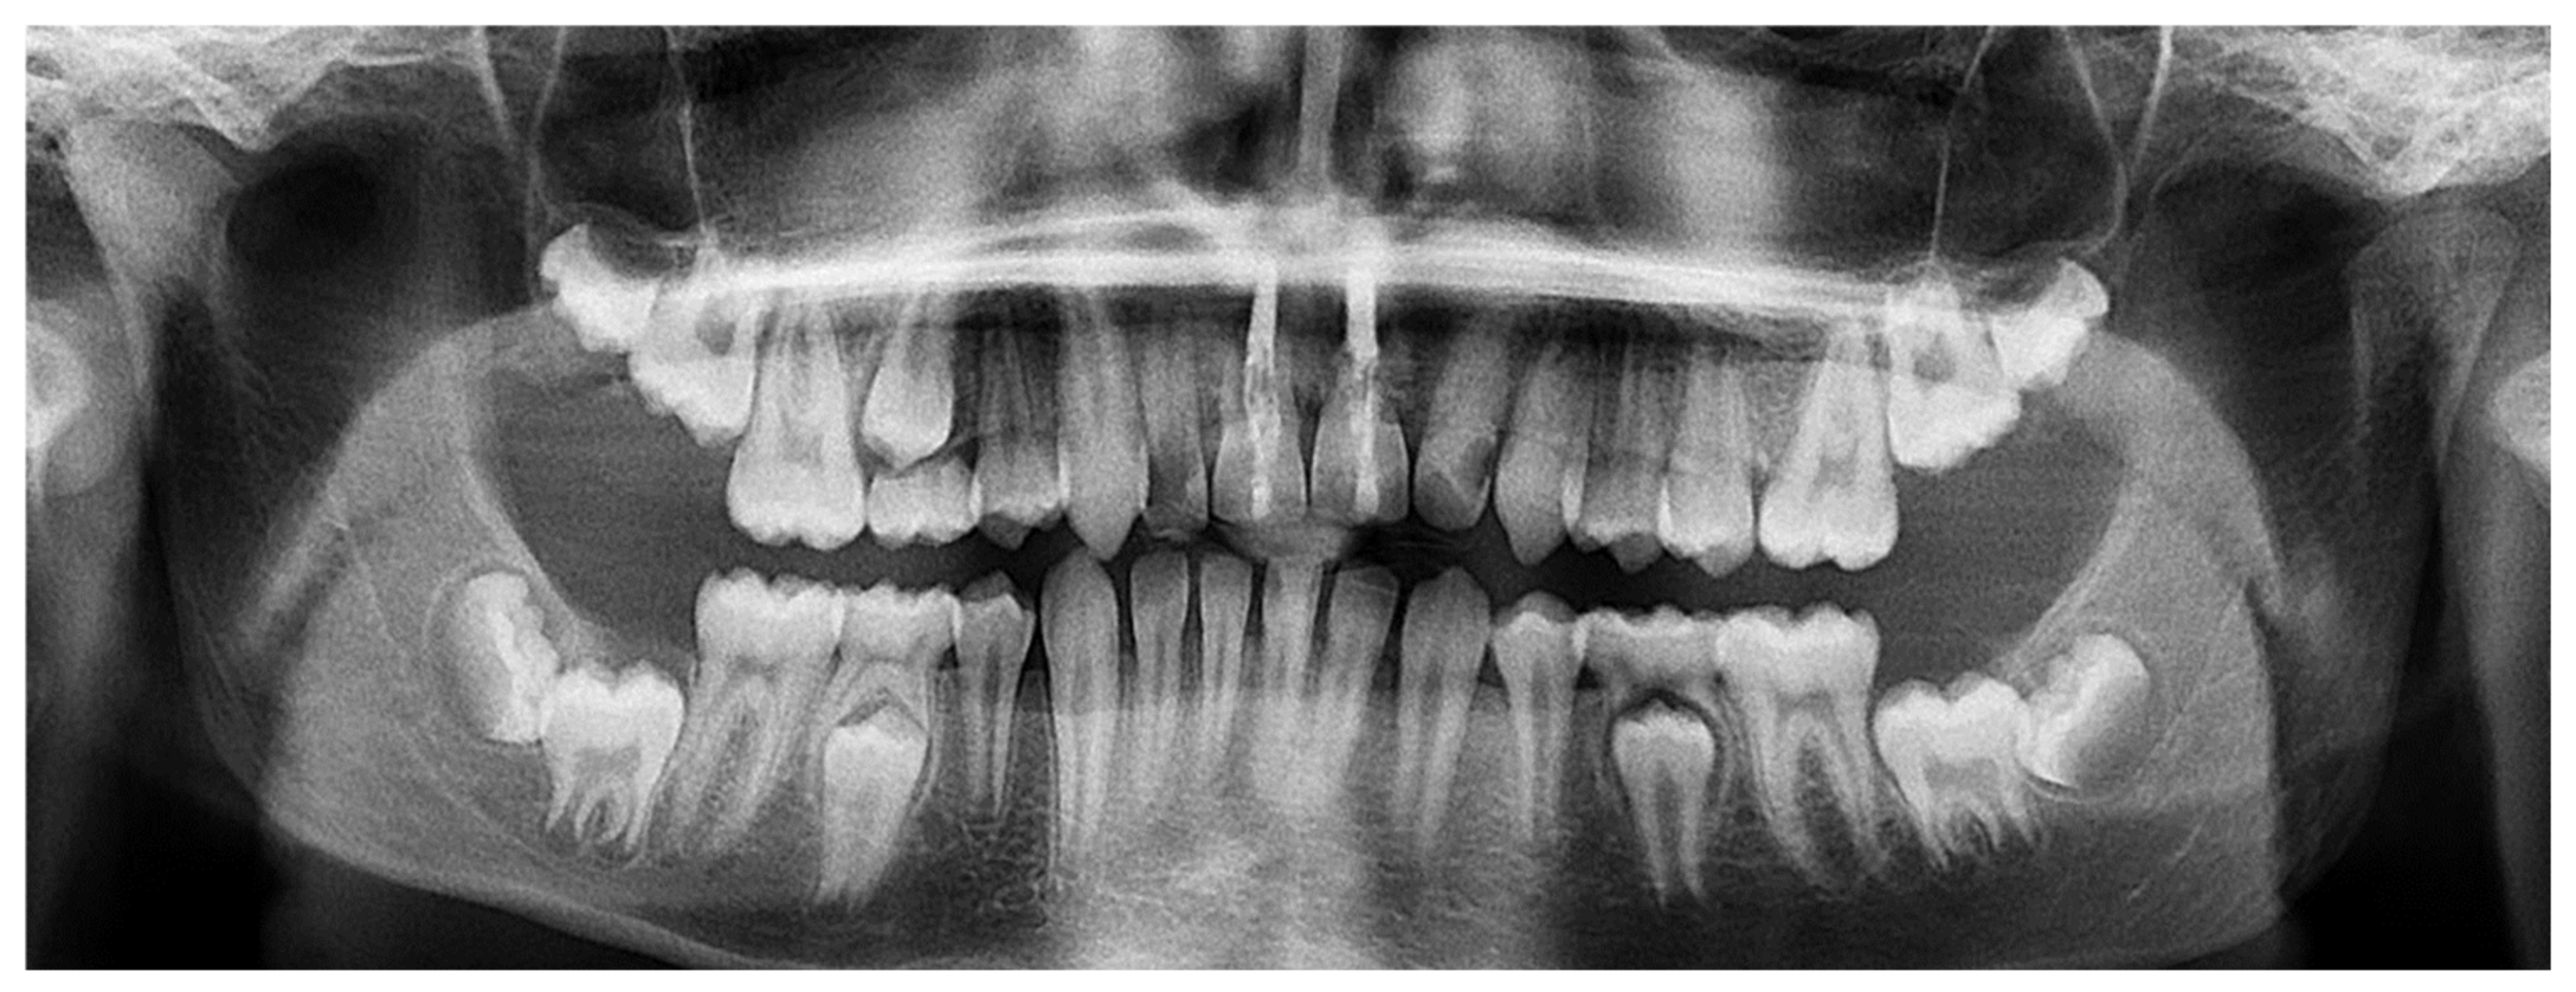

| May 2019: Orthodontic treatment for skeletal class II | Avulsion | |||

| Maintaining space for future implant replacement with resin crown temporization on the orthodontic arch | ||||

| Figure 8 | ||||

| Summer 2019 | Two infectious episodes despite an endodontic re-treatment | |||

| January 2020 | Avulsion | |||